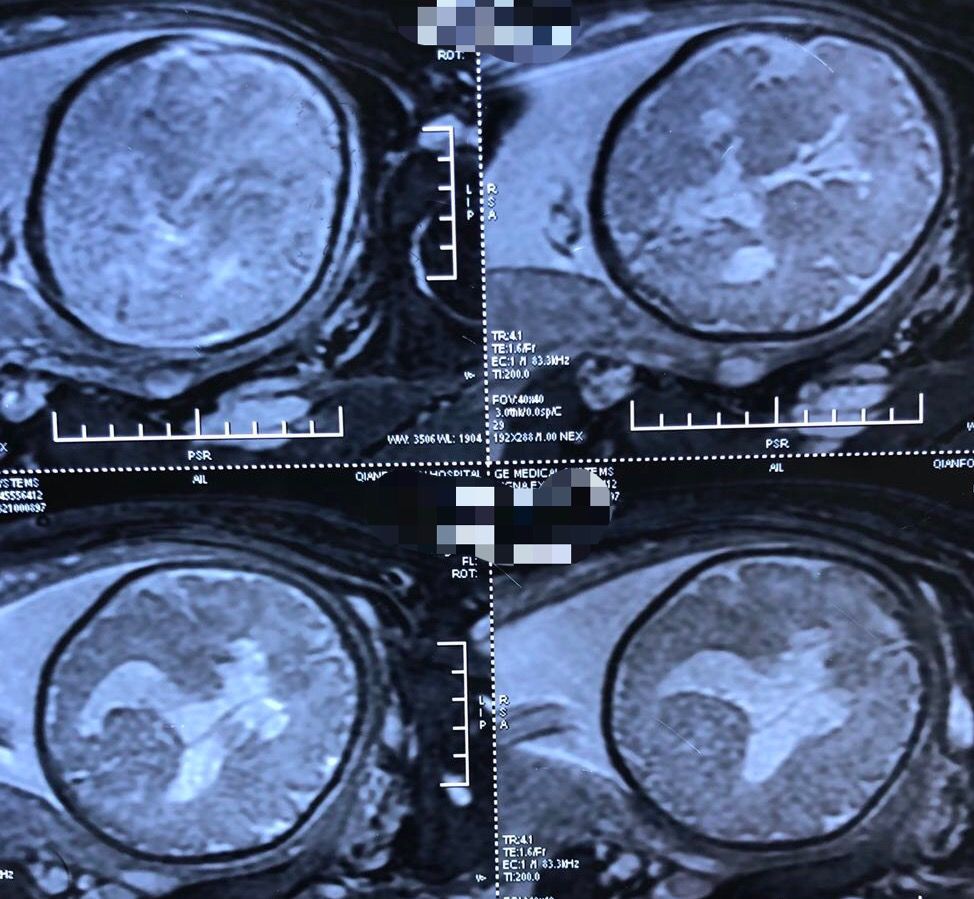

生后3月复查头颅核磁共振

生后3月复查头颅核磁共振